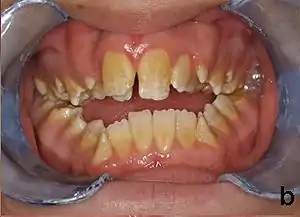

| Amelogenesis imperfecta, hypoplastic type. Note the association of pitted enamel and open bite. | |

People afflicted with amelogenesis imperfecta may have teeth with abnormal color: yellow, brown or grey; this disorder can afflict any number of teeth of both dentitions. Enamel hypoplasia manifests in a variety of ways depending on the type of AI an individual has (see below), with pitting and plane-form defects common.[4] The teeth have a higher risk for dental cavities and are hypersensitive to temperature changes as well as rapid attrition, excessive calculus deposition, and gingival hyperplasia.[5] The earliest known case of AI is in an extinct hominid species called Paranthropus robustus, with over a third of individuals displaying this condition.[6]

- Type 1 - Hypoplastic

- Enamel of abnormal thickness due to malfunction in enamel matrix formation. Enamel is very thin but hard & translucent, and may have random pits & grooves. Condition is of autosomal dominant, autosomal recessive, or x-linked pattern. Enamel differs in appearance from dentine radiographically as normal functional enamel.[20]